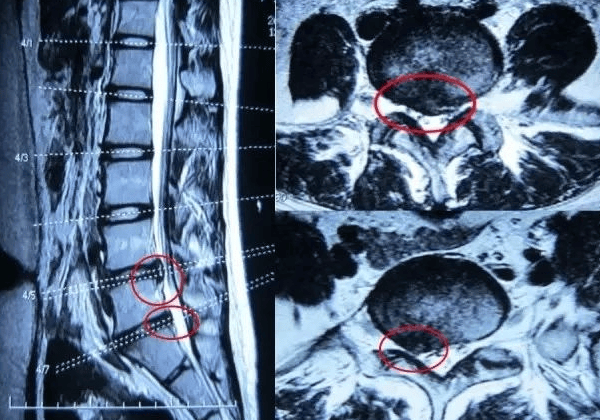

郑州大学第五附属医院中医科一病区主任 徐辉 文/图 门诊上总有患者拿着腰椎片子急着问:“医生,我这都腰突了,应该注意啥?需不需要治疗?” 其实查出腰突以后如果没有症状真不用这么慌,以下几个方法可以防